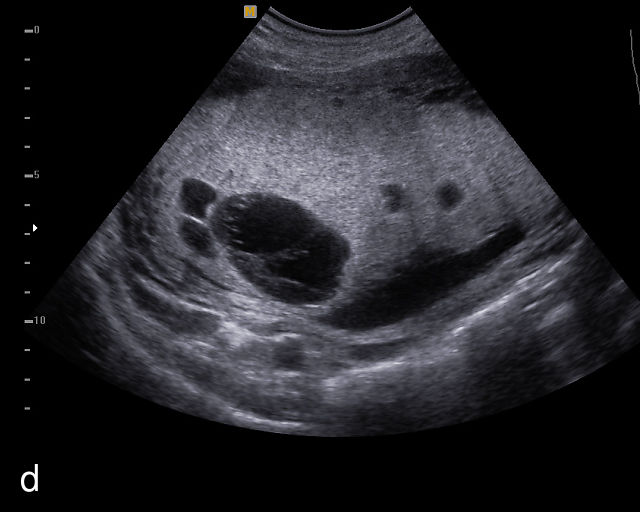

Circumvallate placenta

A circumvallate placenta is one in which the chorionic plate (the fetal surface of the placenta) is smaller than the basal plate, resulting in placental tissue extending beyond the margins of the membrane insertion.9 This creates rolled edges with a cuplike appearance. Rather than inserting at the edges of the placenta, the membranes insert into the fetal surface. In a review of 16 042 placental pathology reports collected over 13 years, Stuijt et al. found that circumvallate placentas were present in 2.2% of cases.159 Circumvallate placentas have been associated with an increased risk of adverse pregnancy outcomes, including FGR, placental abruption, preterm birth and fetal demise.160,161

Sonographically, a circumvallate placenta appears as a placenta with raised, rolled edges, which can be identified on grayscale ultrasound (Figure 13). Additionally, a placental shelf or band may be observed at the placental margin. The differential diagnosis includes amniotic bands, uterine synechiae and uterine septa. However, achieving an accurate prenatal diagnosis can be challenging. An early study by Harris et al. found a poor correlation between the sonographic diagnosis of circumvallate placenta and confirmation on placental examination after delivery.162 In that study, placental sonograms reviewed by expert sonologists showed that 17 of 49 normal placentas were incorrectly diagnosed as probably or definitely circumvallate by one or more observers. Conversely, in a study of 10 patients in which prenatal ultrasound had revealed raised rolled placental edges thought to represent circumvallate placenta, the diagnosis was confirmed on gross placental examination in eight cases.163 This high false-positive rate poses a significant challenge in prenatal ultrasound diagnosis and impacts the interpretation of reported outcomes. The difficulty in achieving an accurate diagnosis likely contributes to the wide range of reported prevalence of circumvallate placenta.

13

(a–e) Grayscale images of circumvallate placentas showing the rolled edges of the placentas.